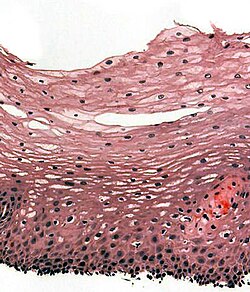

Normal esophagus

General:

- Stratified squamous non-keratinized epithelium.

Normal (esophageal) squamous epithelium:

- Should "mature" to the surface like good stratified squamous epithelium does.

- No nuclei at luminal surface.

- Cells should become less hyperchromatic as you go toward the lumen.

- Mitoses should be rare and should NOT be above the basal layer.

- Inflammatory cells should be very rare.